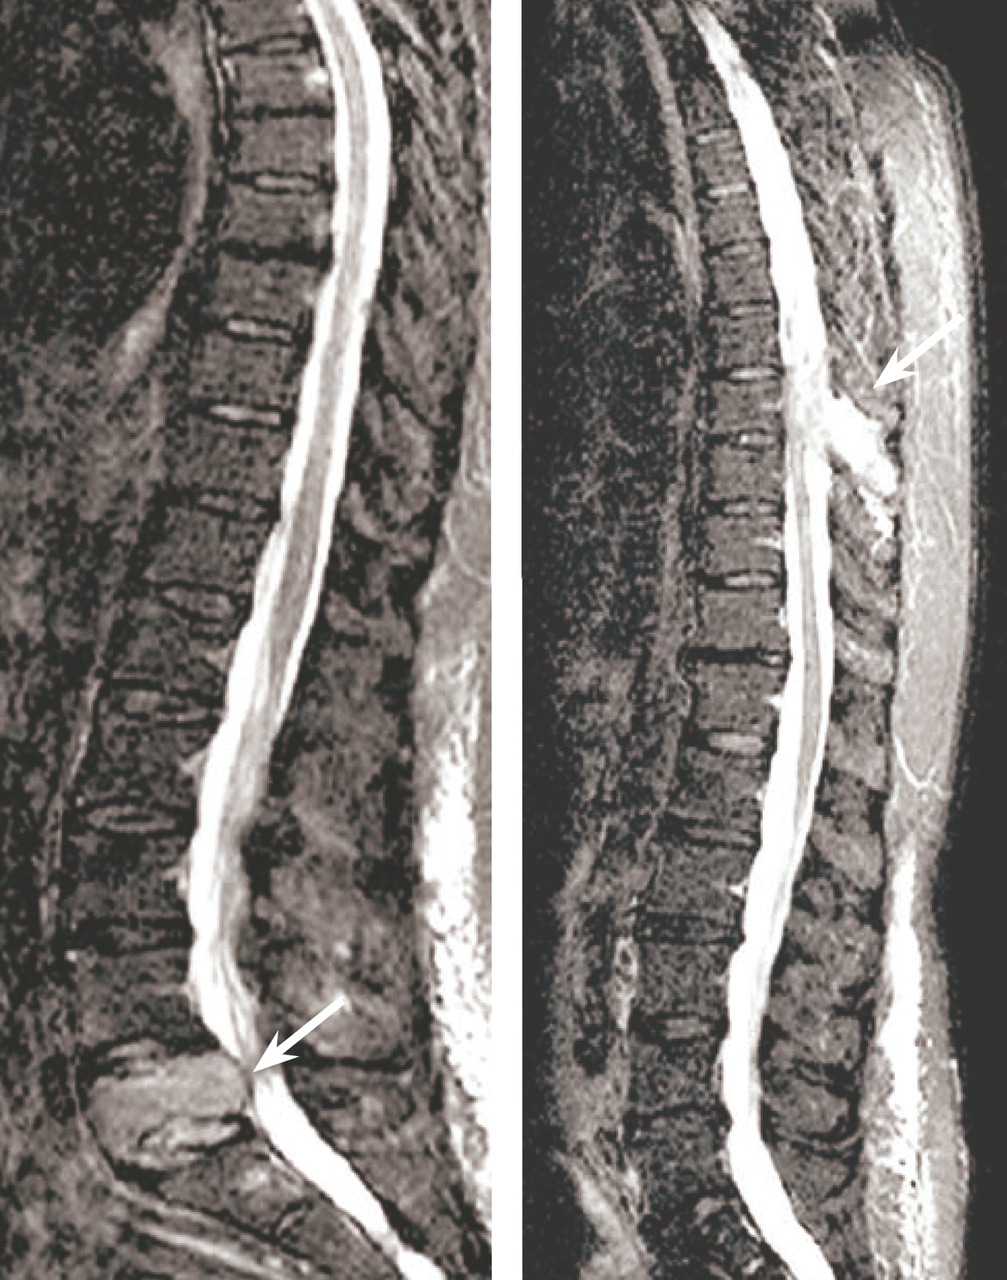

Les clichés standard du squelette axial (crâne, rachis, côtes et bassin) restent encore la référence pour diag­nostiquer une atteinte osseuse mais devraient être remplacés, en raison de leur faible sensibilité, par l’imagerie moderne. Les anomalies évocatrices sont une lyse à l’emporte-pièce (géode ou lacune), visible sur les os plats, associée ou non à une déminéralisation diffuse, ou sur les os longs avec résorption corticale et menace de fracture pathologique (fig. 4). Les lacunes peuvent être totalement asymptomatiques, notamment lorsqu’elles siègent sur le crâne. Les tassements vertébraux, plus ou moins complets, voire en galette, sont toujours symptomatiques. Le scanner du corps entier faible dose devrait remplacer les clichés standard en raison de sa plus grande sensibilité, de sa durée de réalisation plus courte et de sa plus faible dose délivrée d’irradiation. L’IRM du corps entier et le TEP-scan détectent 20 % de lésions supplémentaires par rapport aux clichés osseux standard sous la forme d’images nodulaires en hyposignal T1 et hypersignal T2 et STIR, pour l’IRM (fig. 5), ou de foyers hypermétaboliques correspondant aux lacunes sur le scanner, pour le TEP-scan (fig. 6). Ces examens sont particulièrement utiles dans les formes peu avancées de la maladie (absence d’anomalie sur les clichés standard), pour dépister une épidurite ou confirmer le caractère tumoral du tassement vertébral (IRM) et pour suivre l’évolution sous traitement (réponse métabolique au TEP-scan avec disparition des foyers hypermétaboliques). Leur utilisation est en cours de validation et limitée par leur accessibilité.